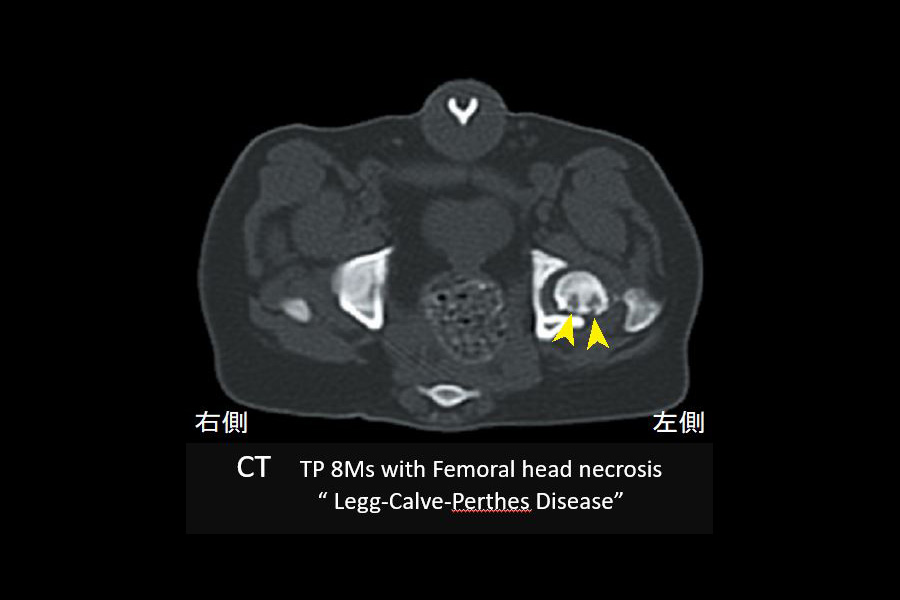

正しく精度の高い運動器治療を行うためには、五感を活かした基礎診断、とりわけ徒手検査や一般的なX線検査診断が重要です。四肢の指(趾)先から体幹に向けての各関節の可動域検査(屈伸運動)は、関節の異常(炎症、関節軟骨の磨耗、靭帯損傷など)や関節周辺組織の異常(軟部組織の腫れ、骨折など)を知るために必須の検査です。また、X線検査では骨折や脱臼、脊椎の異常(椎間の狭窄、変形、奇形、腫瘍性病変など)が明瞭となります。しかし、椎間板ヘルニアや、関節内の靭帯や軟骨損傷、軟骨半月損傷では、CTや関節鏡などの専門機器によるより精度の高い診断が必要です。